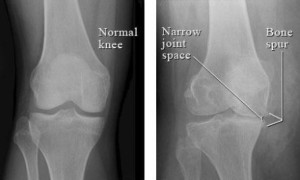

Η διάγνωση της πάθησης γίνεται από τον ορθοπαιδικό ιατρό με την κλινική εξέταση, με ακτινογραφίες που γίνονται σε όρθια θέση και μερικές φορές με μαγνητική τομογραφία και εξετάσεις αίματος.